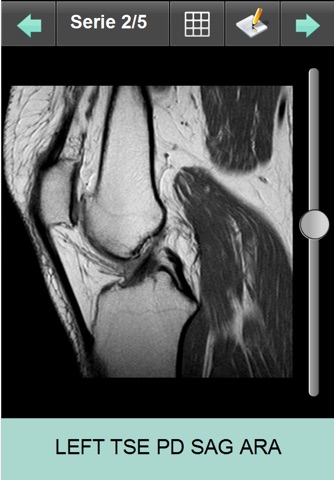

- Sélectionnez Images marquées pour ne charger que les images pertinentes de lexamen (connexion WIFI conseillée pour charger lexamen complet)

Dans longlet Examen :

- Renseignez le numéro dexamen et le mot de passe associé pour accéder aux images de lexamen et à son compte-rendu